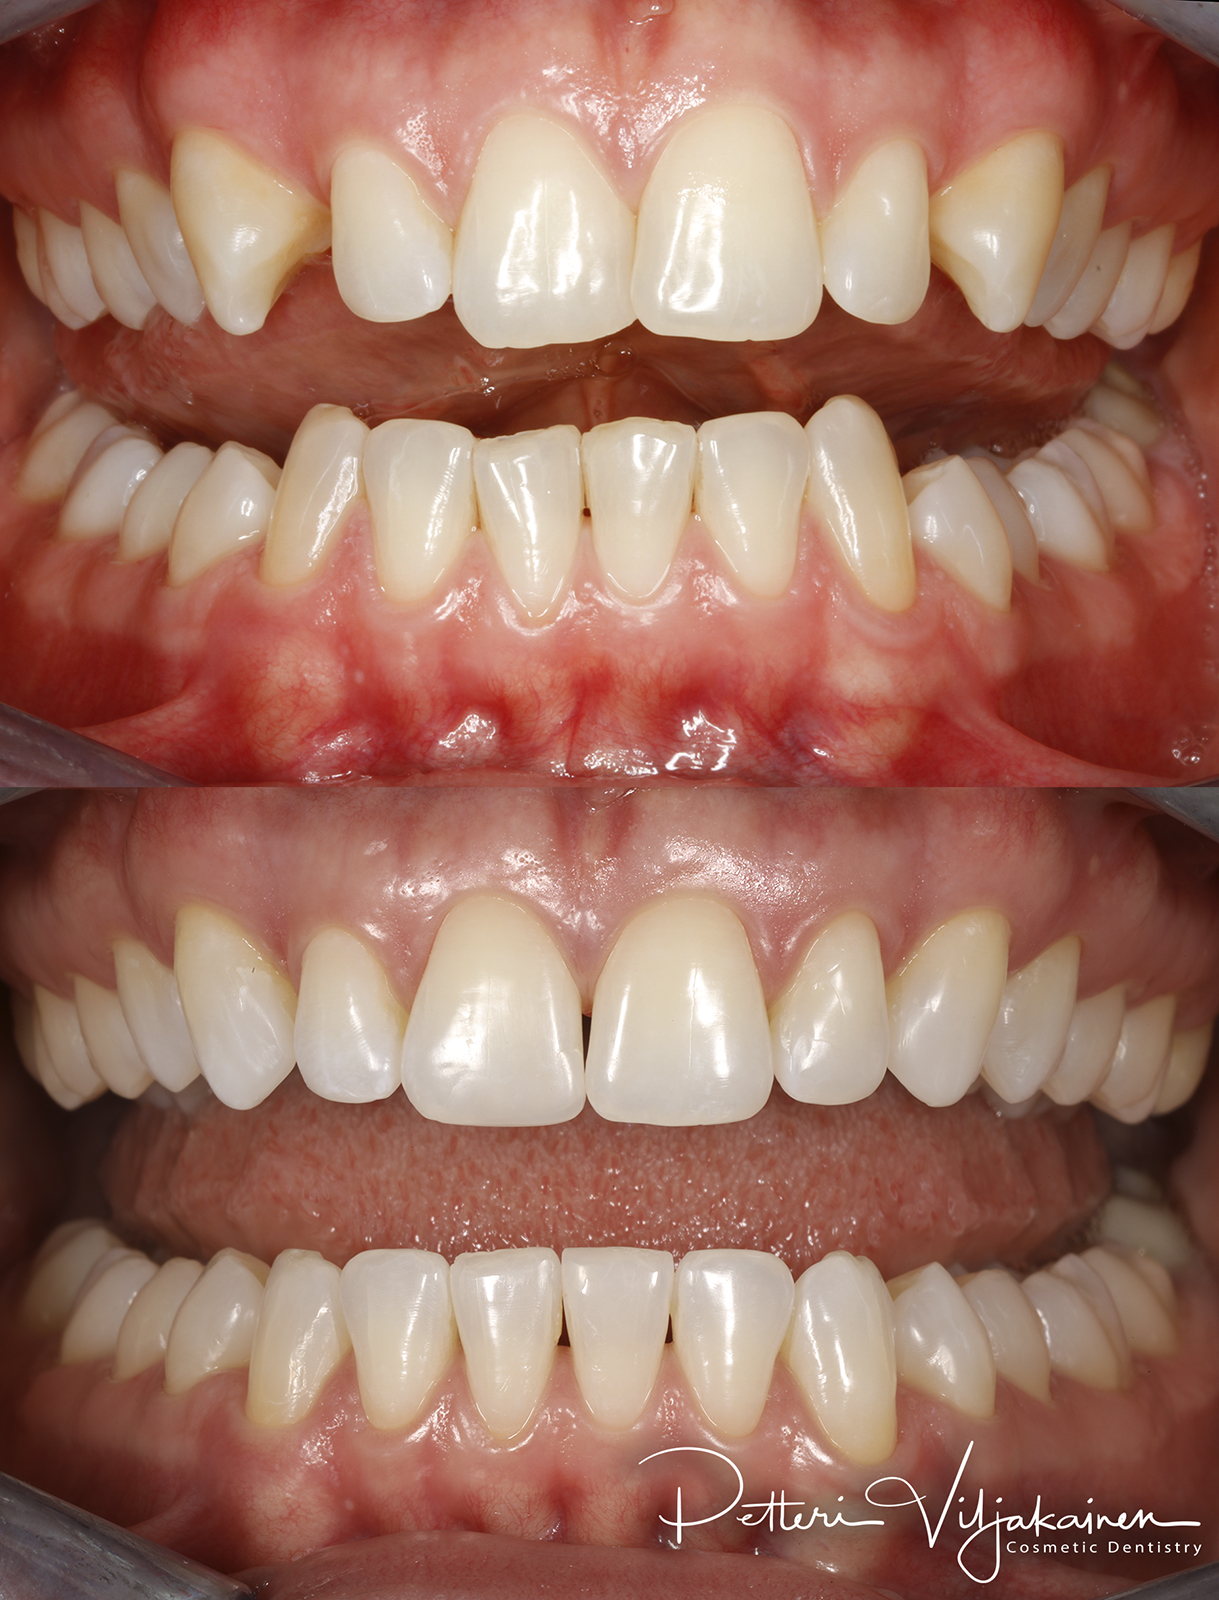

18kk hoito (Comprehensive). Keraamiset kuoret keskimmäisiin yläetuhampaisiin, kerrostusmuoveilla tehty reunimmaiset yläetuhampaat.